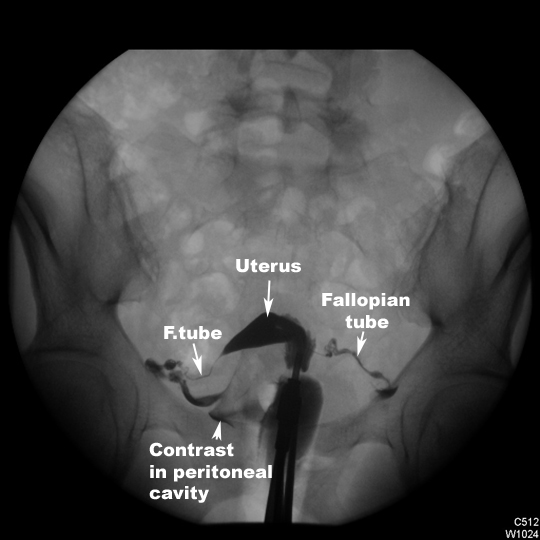

Hysterosalpingogram |

|